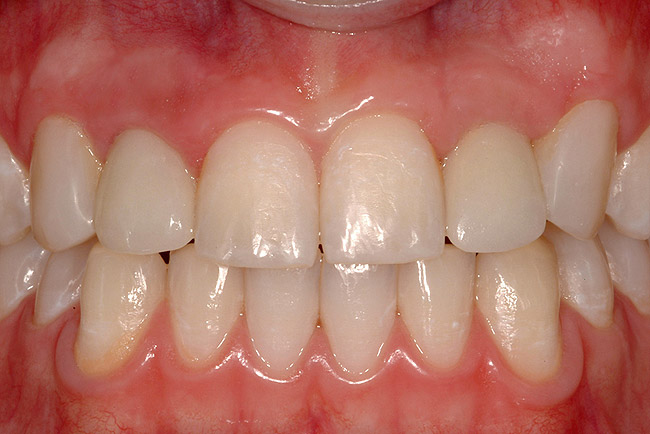

The transitional titanium abutments were left in place for 8 weeks. During this time, the morphologically shaped,.computer-milled abutments supported the interproximal tissue and developed the desired emergence profiles. The.computer-milled abutments were created to a.commodate the adjacent teeth and opposing occlusion, and to aid in the fabrication of the final porcelain-fused-to-metal (PFM) restorations (Figure 20A and Figure 20B). The final crowns were delivered 4 months after implant placement. The radiograph of the emergence profile confirmed the seamless fit of the abutment-implant-crown interfaces (Figure 21). The final restorations were esthetic, functional, and met the needs of the patient (Figure 22A). The re-establishment of the interdental papilla.completed the careful transformation of the flat alveolar crestal tissue into a proper emergence of the clinical PFM crowns, indistinguishable from the surrounding dentition (Figure 22B).

Figure 22a  The final restorations are indistinguishable from the surrounding dentition, demonstrating good emergence and re-creation of the interdental papillae.

Figure 22a

Figure 22b  The final restorations are indistinguishable from the surrounding dentition, demonstrating good emergence and re-creation of the interdental papillae.

Figure 22b